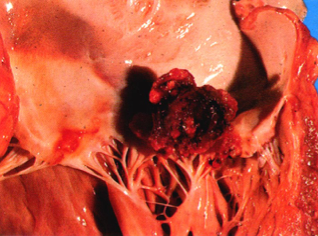

肉眼观,常在原有病变的瓣膜上形成赘生物。病变瓣膜增厚、变形,并发生溃疡,甚至穿孔和腱索断裂,其表面赘生物大小不一,单个或多个,形态不规则呈息肉状或鸡冠状,颜色呈灰黄色或灰绿色,干燥质脆,易破碎和脱落成为栓子,引起栓塞(图2-3)。

图2-3